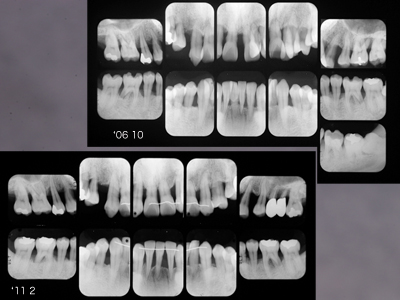

'97初診当時40歳男性。右下6に頬舌側から2度の根分岐部病変が存在。スケーリング、ルートプレーニング、FOPを経て6ヶ月毎のメインテナンスが14年継続しています。

挺出によって垂直ポケットが減少すれば水平ポケットはメインテナンスできるのです。歯間乳頭部にはクリーピングもみられます。

x線写真でも安定しています。

初診時30代男性。「歯並びを治したい」が主訴でしたがプロービングデプス全顎8〜9mmの重度歯周炎でした。歯周治療後全顎pd2~3mmに改善を確認、矯正治療は専門医山田秀樹先生にお願いしました。

矯正治療が終わりました、といわれても上顎犬歯遠心にスペースを残す、やや控えめな歯牙移動、、、それが私の眼には物足りなく思ったものでした。しかし経過を観察すること初診から5年、骨レベルは安定し歯肉はタイトに引き締まってプローブははいらないばかりか付着歯肉が増大してきました。良好な経過から矯正専門医の適切で妥当な判断だったといえます。さすがです。